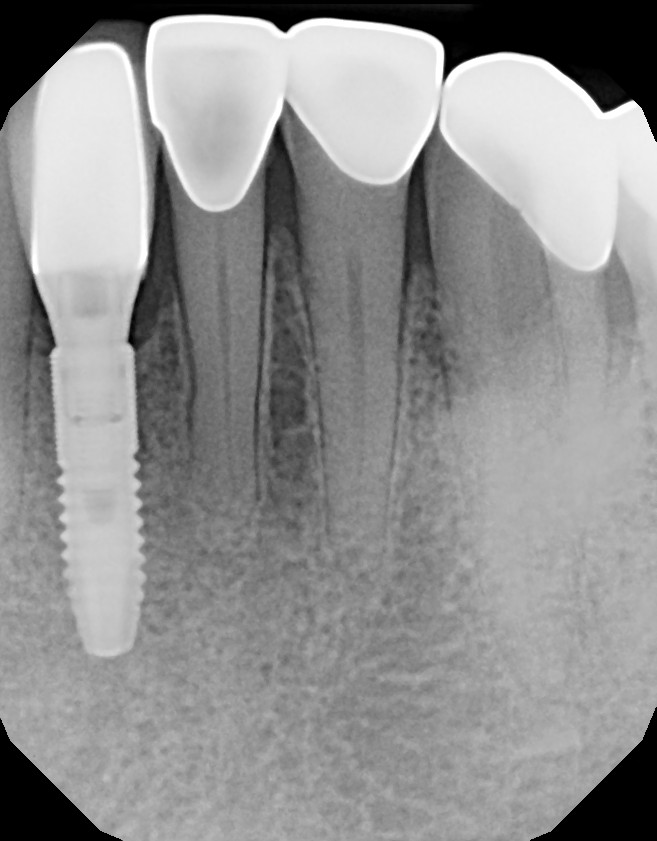

This mouth had recession on just one tooth with very little bone to support the tooth. The area needed support and thickness. The tissue was placed and the area now has thicker tissue to withstand the forces that the patient needs to place on it.